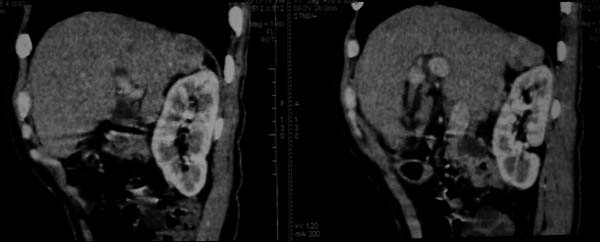

标题: CT16292:男,53岁,上腹部不适2月,B超发现肝内占位病变。 [打印本页]

标题: CT16292:男,53岁,上腹部不适2月,B超发现肝内占位病变。

符合肝ca增强,\"快进快出\";肝叶比例失常,右叶萎缩,肝裂增宽,脾大,肝硬化可能.

肝脏体积变小,肝裂增宽,分布异常,肝尾叶增大,脾肿大,考虑肝硬化可能性大,右肝病灶呈现早期充盈,延迟强化考虑肝内胆管细胞癌可能,不除外血管瘤

肝叶比例失调,左叶增大,肝裂增宽,脾脏增大,门脉增宽,肝右叶包膜下多发结节样阴影,增强虽说强化幅度不大,但还是符合快进快出特点;考虑肝硬化、脾大、结节型肝癌。胆管细胞癌多有延时强化、肝包膜凹陷征、周围胆管扩张等特点,本例明显不符;故不考虑。